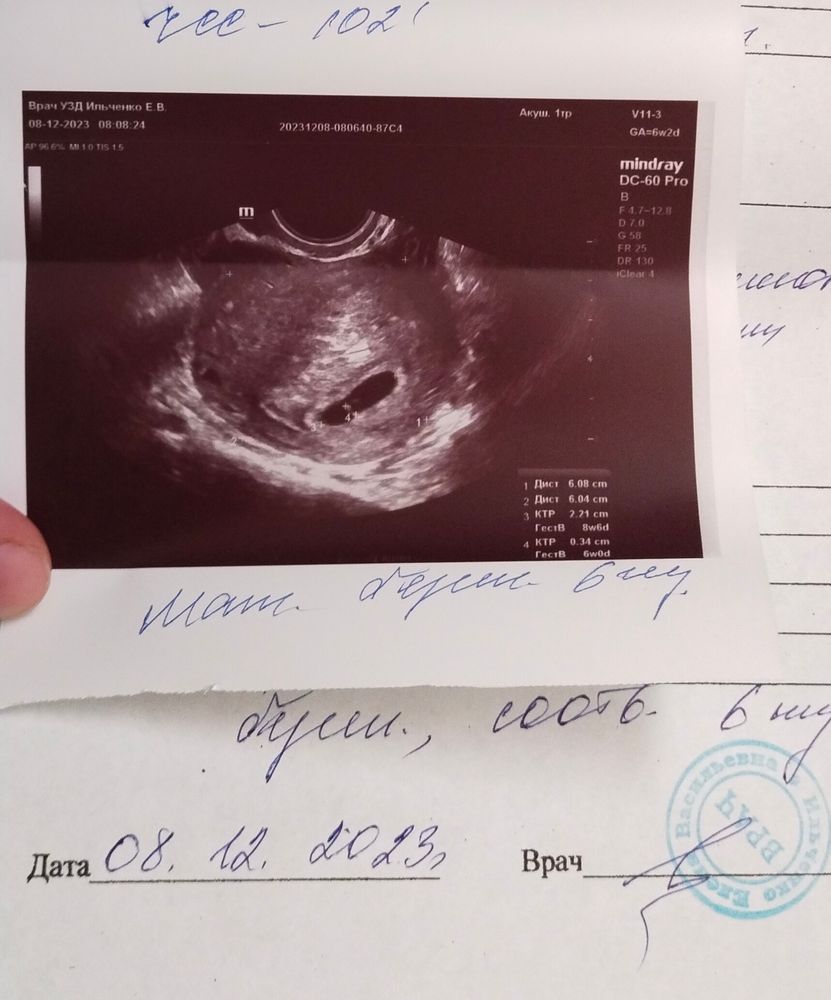

Ну вот и настало день УЗИ и у мужа день рождения 🥰 ждала было страшно .По месячным срок 6,2 по УЗИ 6 недель ЧСС 102 эмбрион 3мм ,сказала что для такого срока ЧСС нормально,(в интернете пишут тоже самое). Самочувствие так себе тошнота постоянно ну рвоты пока слава Богу нету, помогают мармеладки🤭 . В понедельник иду в женскую консультацию вставать на учёт,пдр на 31 июля🥰

Ну и фоточка с УЗИ🥰